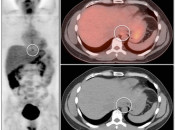

- Maximum Intensity Projection (MIP)

- Fusion of Images

- All Images Viewed in 3 Planes